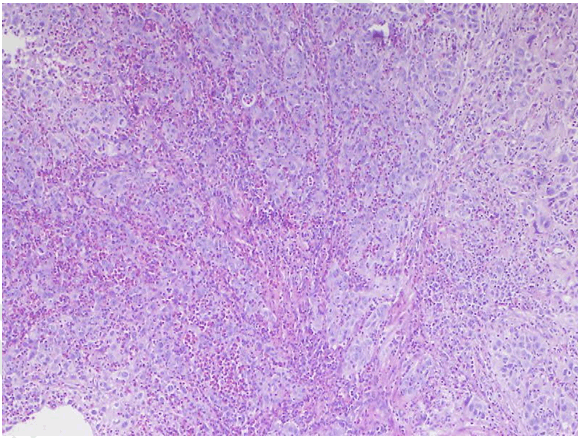

Microscopic examination of the biopsied specimen of the tumor revealed sheets of large cells with abundant inflammatory infiltration consisting predominantly of eosinophils and lymphocytes characterized by large nuclei with prominent nucleoli. Cells showed a moderate amount of granular or clear cytoplasm. We observed a high mitotic rate and many abnormal mitoses and distinct cell membrane stained well by PAS stain. Finally, the presence of necrosis area was noted. The pathological diagnosis of glassy cell carcinoma was made (Figure 1) (Figure 2) (Figure 3).

Figure 2: Presence of large cells characterized by large nuclei with prominent nucleoli and abundant inflammatory infiltration consisting predominantly of eosinophils and lymphocytes and giving a ground-glass appearance. Frequent mitosis was seen and same abnormal mitoses (H&E stain, x400).

Thus, the diagnosis is pathological. Histologically, the glassy cell carcinoma is composed by cells arranged in nests and cords separated by fibro vascular septa. The stromal infiltration is predominantly composed of eosinophil cells and plasma cells with an admixture of lymphocytes, giving a very characteristic appearance.

The cytoplasm's cells are eosinophilic, sometimes amphophilic, with a ground glass appearance and distinct cell membrane stained well by PAS stain. The nuclear membrane is dense. The majority of the nuclei are large, vesicular and hyper chromatic, round to oval, containing exceptionally large and prominent nucleoli [2][3].

Mitotic activity is important with cellular pleomorphism and numerous abnormal mitoses. Focal squamous or glandular differentiation may be seen but not in the reported case. Small foci of necrosis are frequently present as shown in the related case.